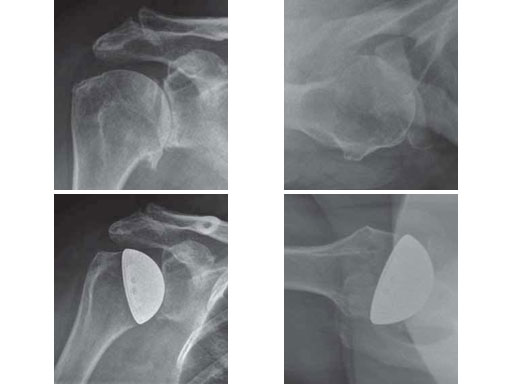

The EPOCA resurfacing head distinguishes itself not only by its anatomical geometry and its very thin surface, but also by its unique fixation design. A central crown anchors the hydroxyapatite coated prosthesis in a press-fit technique in the peripheral parts of the humeral head. In contrast to the central area which is used by most pegs fixed cups the peripheral area shows a better cancellous bone quality especially in osteoporotic conditions. To date, loosening of the EPOCA resurfacing head has not been observed in larger series (Fig 4).

67-year-old female with a primary omarthrosis on the right side.

Case provided by Norbert P Sdkamp, Martin Jaeger, Freiburg, DE, Ralph Hertel, Bern, CH

Fig 4ab Fracture situation in conventional x-rays.

Fig 4cd Implantation of a resurfacing head type EPOCA.